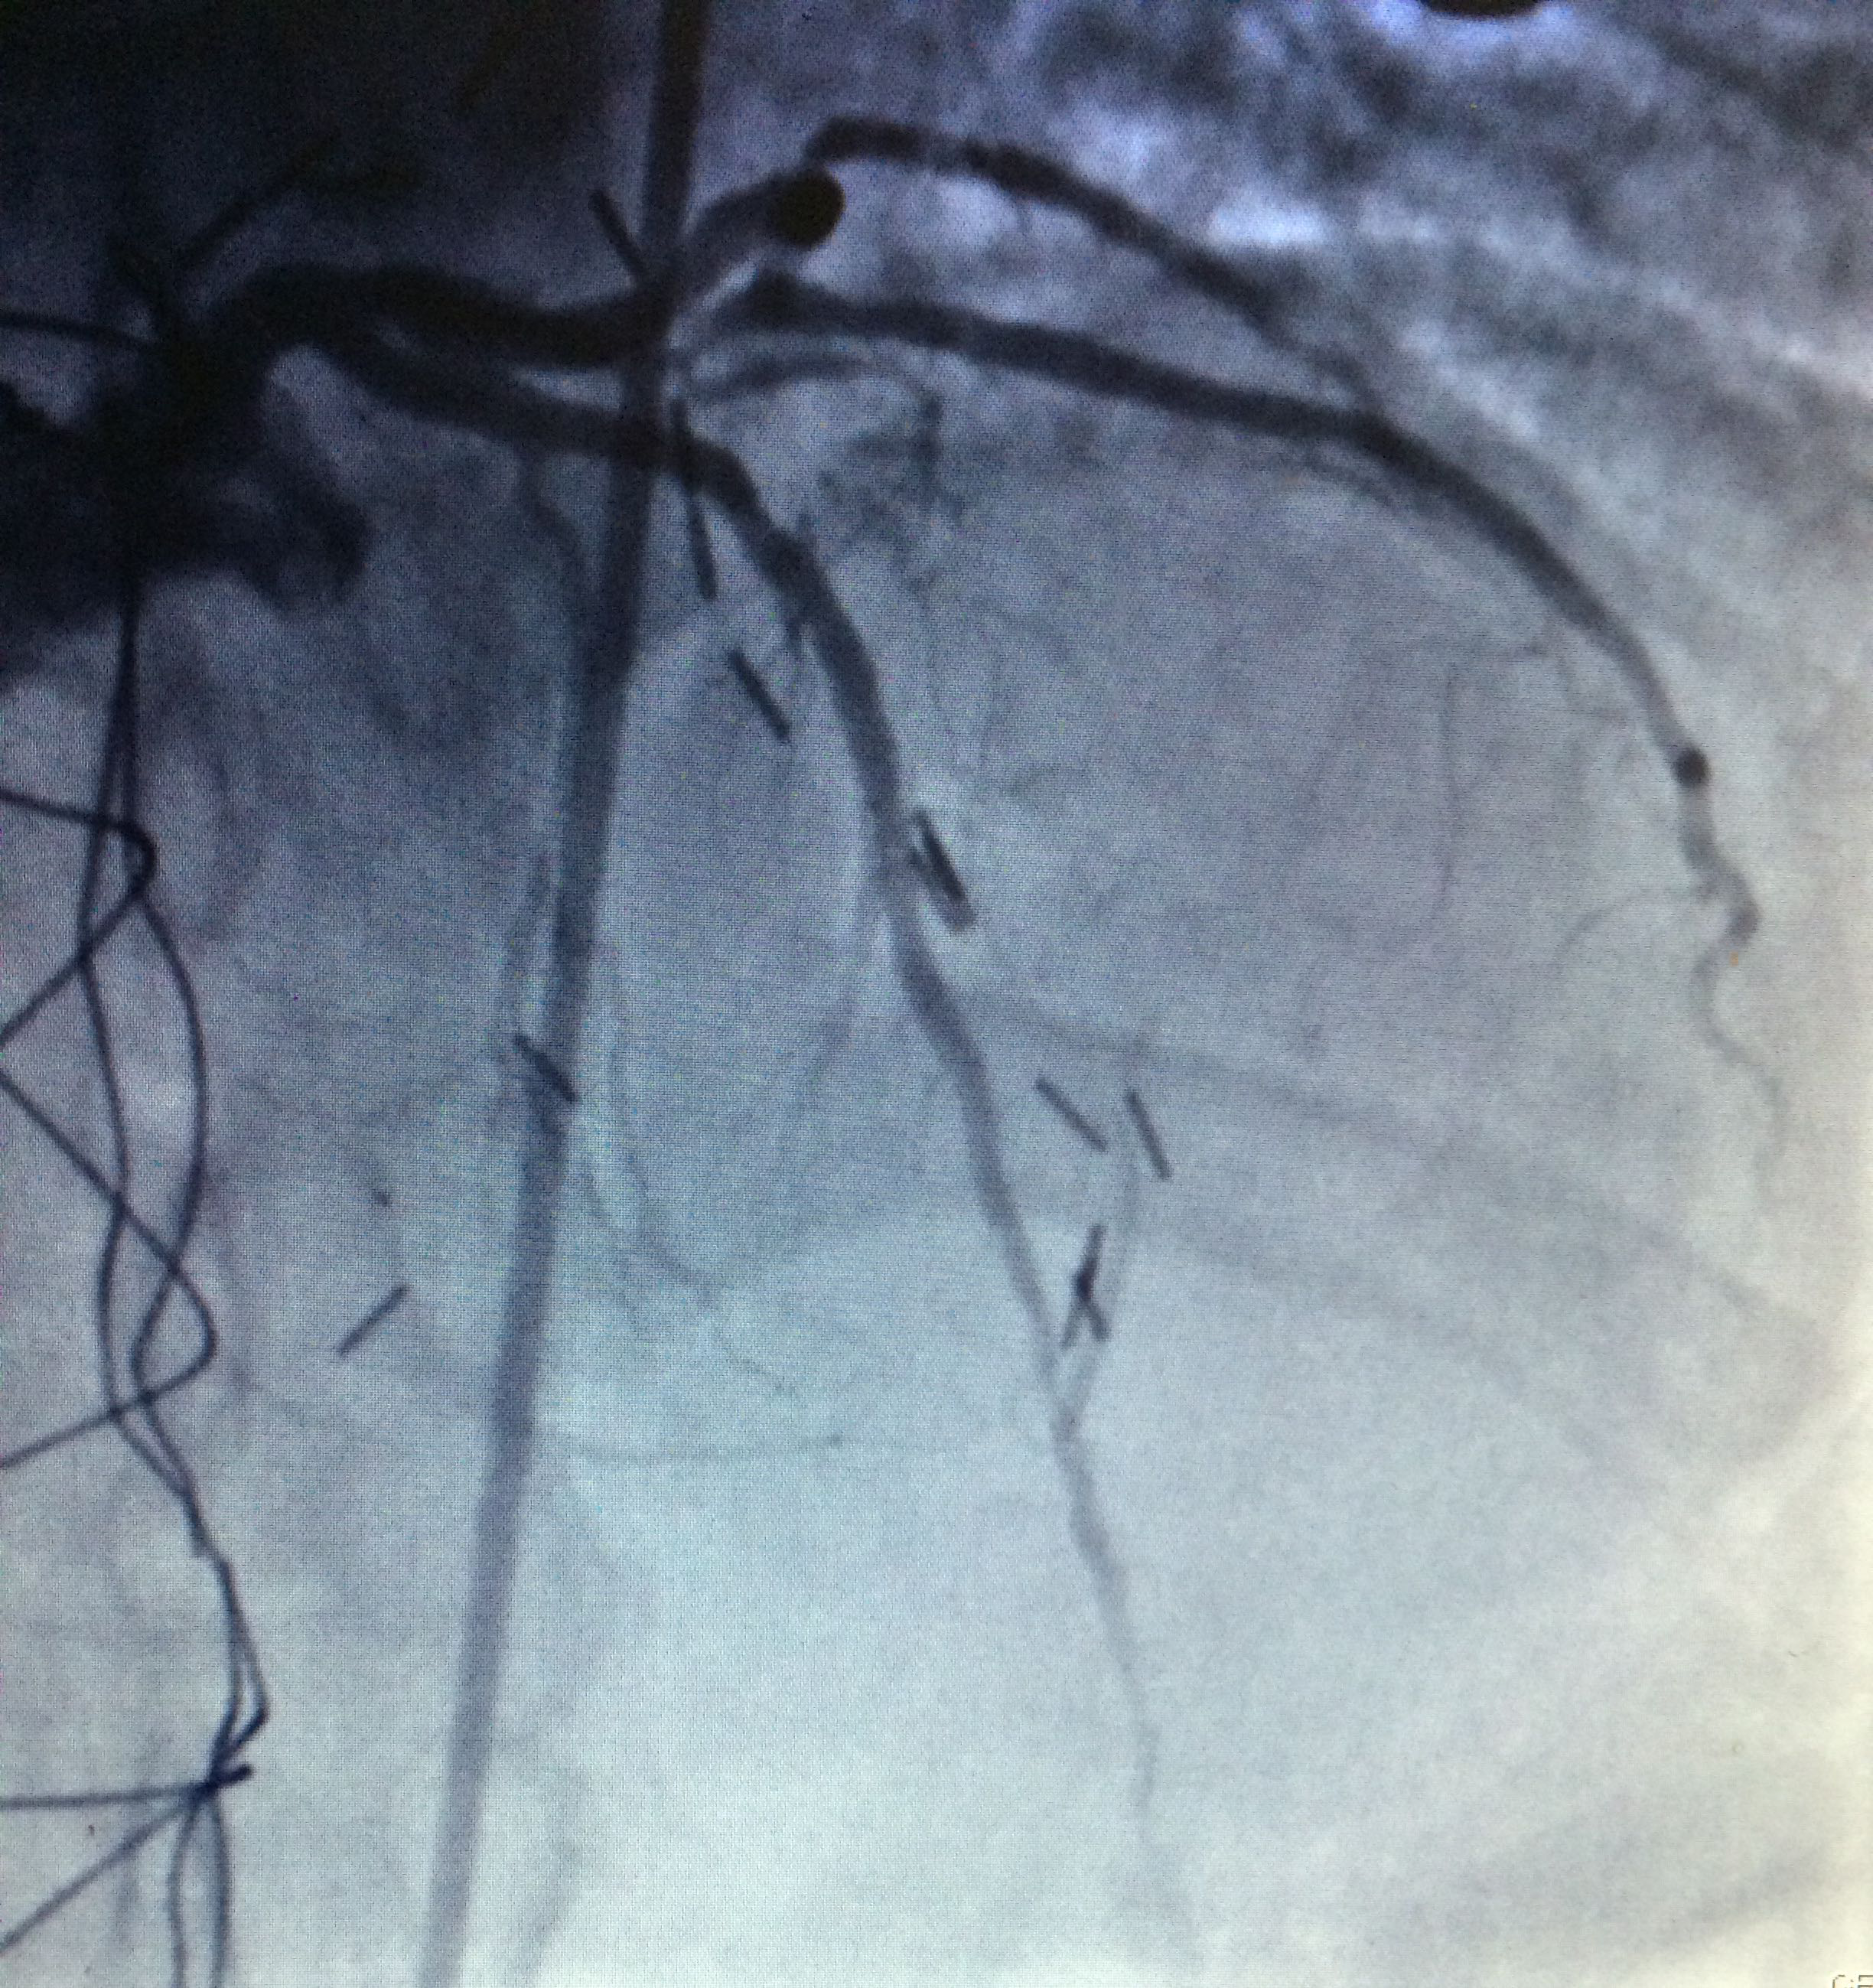

Figure 3 Through a conventional right femoral approach, the left coronary ostium was canalized using a 4.0 6Fr Launcher guiding catheter (Medtronic). Subsequently, a floppy microguide at the level of the anterior left descending artery was used to cross the lesion. Balloon dilation was performed to open the vessel starting with a 1.5x18mm Sprinter balloon (Medtronic) followed by a 2.0x22mm to finally deploy a 2.5x18mm Endeavor stent at 18atm for 10 seconds at the level of left anterior descending artery obtaining a satisfactory angiographic result.

Through a conventional right femoral approach, the left coronary ostium was canalized using a 4.0 6Fr Launcher guiding catheter (Medtronic). Subsequently, a floppy micro guide at the level of the anterior left descending artery was used to cross the lesion. Balloon dilation was performed to open the vessel starting with a 1.5x18mm Sprinter balloon (Medtronic) followed by a 2.0x22mm to finally deploy a 2.5x18mm Endeavorstent at 18 atm for 10seconds at the level of left anterior descending artery obtaining a satisfactory angiographic result (Figure 3-6).

Figure 4 Through a conventional right femoral approach, the left coronary ostium was canalized using a 4.0 6Fr Launcher guiding catheter (Medtronic). Subsequently, a floppy microguide at the level of the anterior left descending artery was used to cross the lesion. Balloon dilation was performed to open the vessel starting with a 1.5x18mm Sprinter balloon (Medtronic) followed by a 2.0x22mm to finally deploy a 2.5x18mm Endeavor stent at 18atm for 10 seconds at the level of left anterior descending artery obtaining a satisfactory angiographic result.